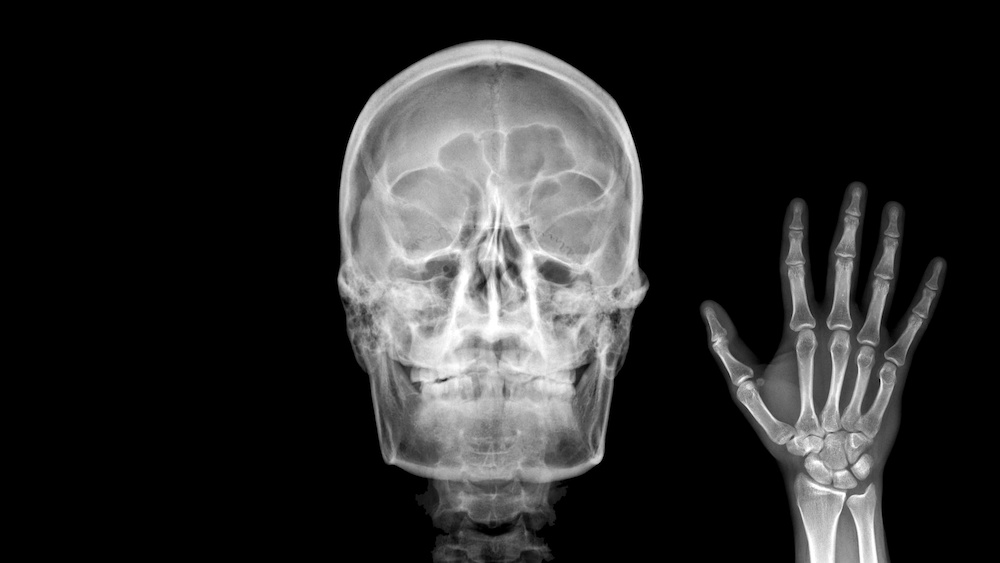

By picking the proper X-ray energies to optimize transmission and contrast, we can take images of all sorts of things. Generally, hard X-rays can image extremely dense or thick objects, while soft X-rays can image thin or low-density materials. Airport scanners use hard X-rays to look for metal in bulging suitcases. Different atoms and molecules pass X-rays somewhat differently, too. Medical X-rays use moderately hard X-ray energies to penetrate skin, bones, and teeth.